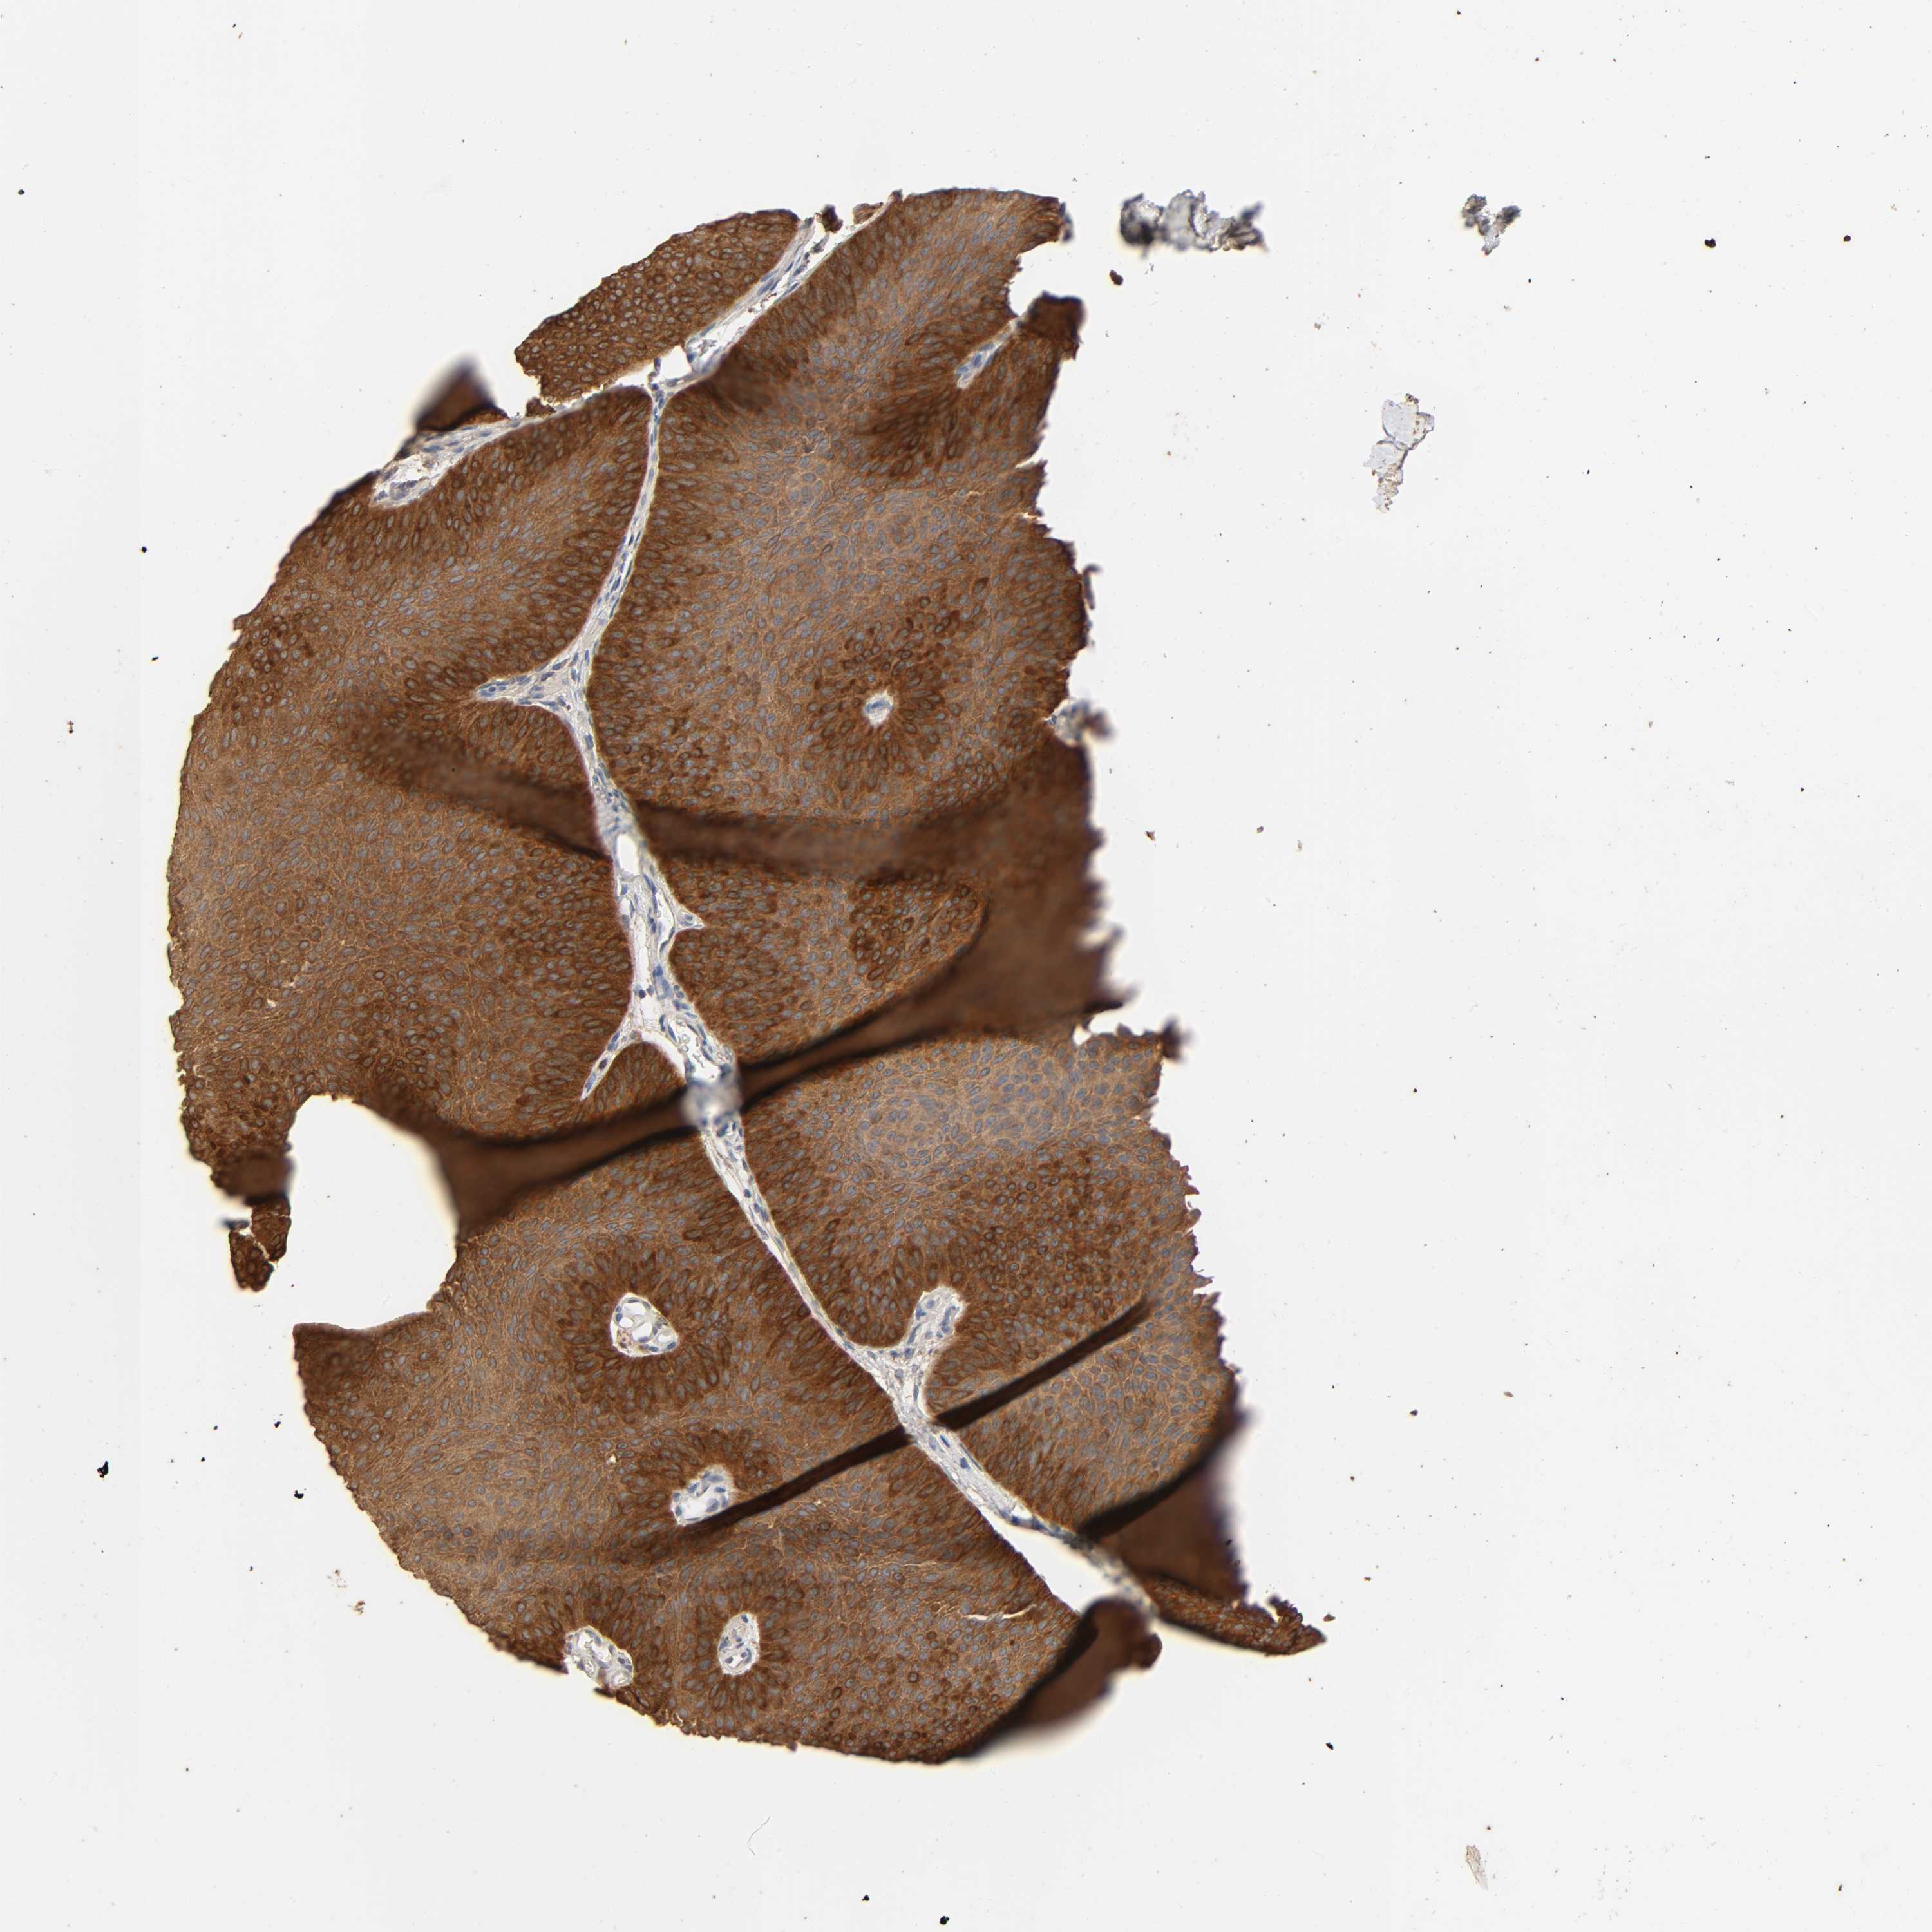

UROTHELIAL CANCER - Protein expressioni

A mouse-over function shows sample information and annotation data. Click on an image to view it in a full screen mode. Samples can be filtered based on level of antibody staining by selecting one or several of the following categories: high, medium, low and not detected. The assay and annotation is described here.

Antibody stainingi

Antibody staining in the annotated cell types in the current human tissue is reported as not detected, low, medium, or high, based on conventional immunohistochemistry profiling in selected tissues. This score is based on the combination of the staining intensity and fraction of stained cells.

Each image is clickable and will lead to virtual microscopy that enables deeper exploration of all samples and also displays staining intensity scores, fraction scores and subcellular localization as well as patient and tissue information for each sample.

Antibody HPA000962

Antibody HPA004119

Urothelial carcinoma, High grade

Urothelial carcinoma, Low grade